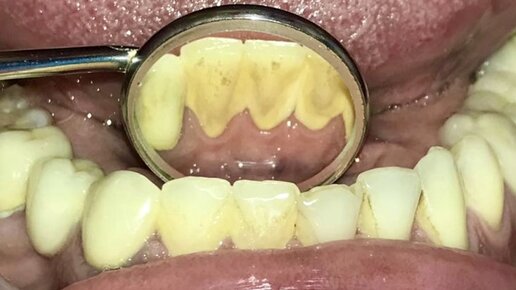

Зубной налет и зубной камень — распространенные проблемы, с которыми сталкиваются многие люди. Их присутствие не только ухудшает внешний вид зубов, но также приводит к серьезным болезням зубов и десен. В этой статье расскажем об эффективных способах избавления от зубного налета и зубного камня, а также предотвращения их появления. Что такое зубной налет и зубной камень Зубной налет — липкий слой, который появляется на эмали в результате длительного неправильного ухода за полостью рта. Основная...

Раньше думала, что налёт на зубах у меня образуется от дурной привычки. Бросила курить несколько лет назад и зубы, конечно же, стали белее, но налёт-то никуда не делся. Что такое зубной налёт на самом деле? По сути, это биологическая плёнка. Она формируется из органических соединений и образуется и в других системах организма. Для зубной эмали такая биопленка не несёт вреда до определенного момента — пока в ней не начинают размножаться бактерии и грибковые микроорганизмы. Появляется запах изо рта, налёт приобретает жёлтоватый оттенок, со временем прессуется, твердеет, образуются зубные камни...